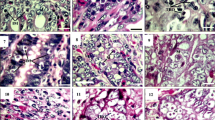

7.1 % of the morphotype II larvae (4/56) displayed pathogenic potential, in accordance with the aforementioned description. Two of these larvae, one of A. physeteris and one of A. paggiae, penetrated the stomach wall and were found within the abdominal cavity, with the first one producing a small lesion with blood vessel breakage (1 mm2) (Fig. 2b). The other two larvae, also of the A. physeteris and A. paggiae species, were found attached to the rodent’s stomach wall (Fig. 2c), with the latter causing a lesion with vascular damage (1 mm2) (Table 2). The majority of the L3 larvae of morphotype II were found in the intestine (51.8 %; 29/56) with the caecum being the least frequent location (8.9 %; 5/56). In contrast, 44.0 % (11/25) of the morphotype I larvae demonstrated pathogenic potential; details of this classification and location of both larvae types in the animal upon necropsy are shown in Table 2.

A. physeteris is the predominant anisakid species of morphotype II found in the Iberian Peninsula coasts, followed by A. paggiae. Their prevalences are much lower than those of species of morphotype I (Valero et al. 2000; Mattiucci et al. 2007). A. brevispiculata is not well represented here, given that only one larva has been found in a blue whiting from the Atlantic Coast and this was the first time that this species has been cited along the coasts of the Iberian Peninsula. It was also the first time that A. paggiae was found in different fishing points of the Mediterranean, thus broadening the geographic zone and host organisms of this species. Despite the fact that the presence of Anisakis of morphotype II is apparently low, a case of human infection in Spain has been reported and allergic reactions have been attributed to this morphotype (Clavel et al. 1993; Valero et al. 2000, 2003). In our experimental model using Wistar rats (Romero et al. 2013; Zuloaga et al. 2013), 7.1 % (4/56 L3) of the morphotype II larvae penetrated or were found attached to the animal’s gastric wall, and therefore, A. physeteris, like A. paggiae were responsible for lesions with signs of vascular damage (Table 2). This preference for the wall of the stomach was also observed in the Anisakis morphotype I species (Fig. 2a) (Romero et al. 2013).

The obtained results reveal that pathogenic potential is linked to the morphotype or species is linked to the larva’s morphotype or species. Thus it was found that the morphotype II larva had a 90 % lower risk of penetrating than morphotype I larva (CI 95 %: 64 to 97). In addition, as seen in Table 2 and Fig. 2, morphotype II larvae produced less vascular damage, as found in previous studies (Romero et al. 2012, 2013). In our study, morphotype I larvae were 42 times more likely to produce lesions than the morphotype II larvae (p = 0.001) (Fig. 2).